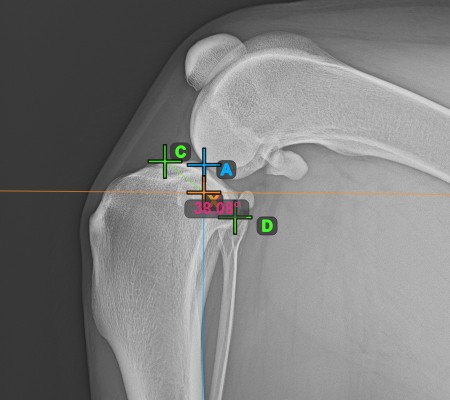

Fejezze be a TPA szög mérését a tibia fejének (tibia plató) legalacsonyabb pontjának megjelölésével. A TPA szög automatikusan kiszámításra kerül a tibia platón lévő két pontot összekötő vonal és a tibia hosszanti tengelyére merőleges vonal közötti szögként.

A lenti kép a tibia plató legalacsonyabb pontjának szokásos elhelyezkedését és a TPA szög automatikusan kiszámított értékét ábrázolja.